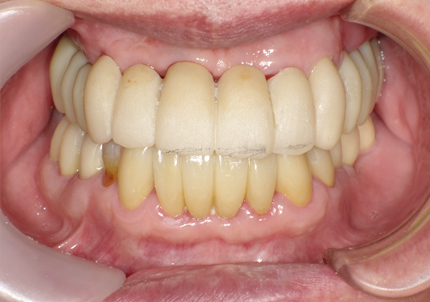

【受傷前口腔内写真】

【受傷後最終補綴物装着】

前歯の受傷前の歯肉の膨らみが、抜歯後にも変わらない状態を維持してインプラント治療されています。患者様、術者も結果がとても良いと満足しています。

13. 最終補綴物装着より4年経過 (2024年10月18日)